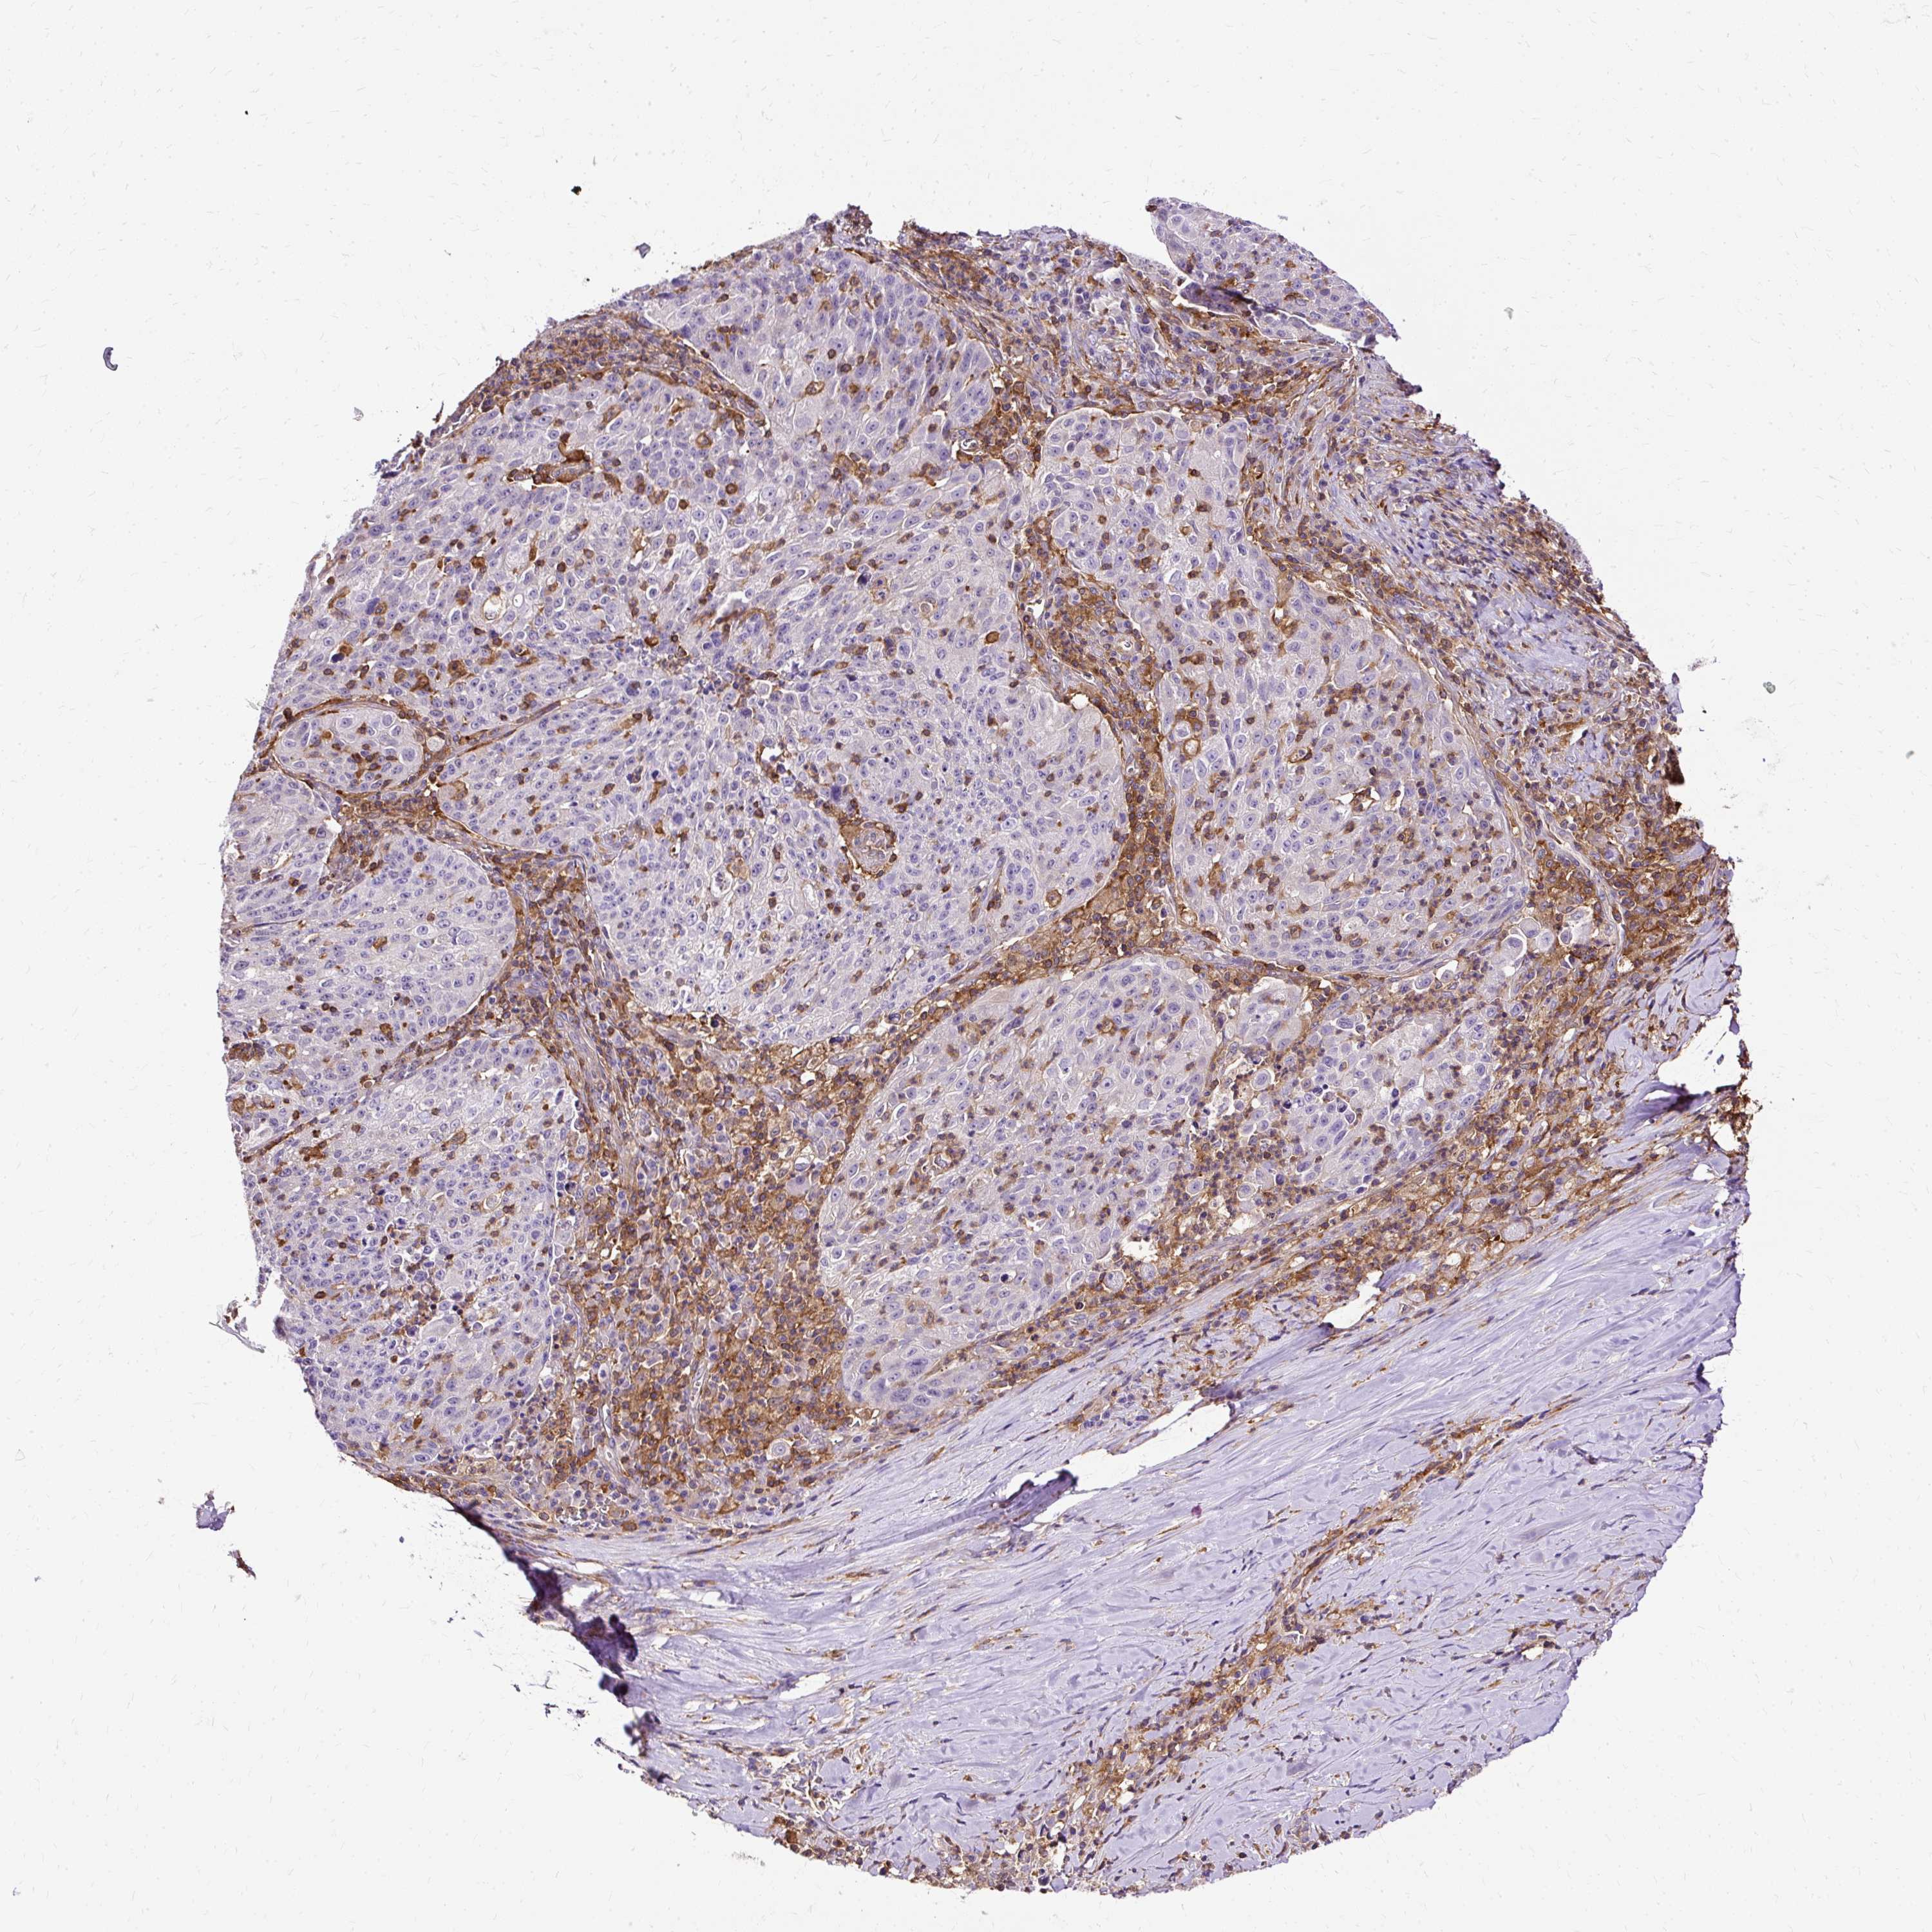

LUNG SQUAMOUS CELL CARCINOMA (TCGA) - Interactive survival scatter ploti

The Survival Scatter plot shows the clinical status (i.e. dead or alive) for all individuals in the patient cohort, based on the same data that underlies the corresponding Kaplan-Meier plots. Patients that are alive at last time for follow-up are shown in blue and patients who have died during the study are shown in red.

The x-axis shows the expression levels (FPKM) of the investigated gene in the tumor tissue at the time of diagnosis. The y-axis shows the follow-up time after diagnosis (years). Both axes are complimented with kernel density curves demonstrating the data density over the axes. The top density plot shows the expression levels (FPKM) distribution among dead (red) and alive patients (blue). The right density plot shows the data density of the survived years of dead patients with high and low expression levels respectively, stratified using the cutoff indicated by the vertical dashed line through the Survival Scatter plot. This cutoff is automatically defined based on the FPKM cutoff that minimizes the p-score. The cutoff can be changed by dragging the vertical line or by entering a cutoff value in the square labeled "Current cut-off".

Under the Survival Scatter plot the p-score landscape (black curve; left axis) is shown together with dead median separation (red curve; right axis). Dead median separation is the difference in median mRNA expression between patients who have died with high and low expression, respectively. It is calculated as follows: median FPKM expression of dead patients with high expression - median FPKM expression of dead patients with low expression. This is intended to aid the user in visually exploring custom cutoffs and the associated p-scores and dead median separation.

Individual patient data is displayed and can be filtered by clicking on one or more of the category buttons on the top of the page. Categories describing expression level and patient information include: high, low, alive, dead, female, male and tumor stages. The scale of the x-axis can be toggled between linear and log-scale by clicking on the "x log" button. Mouse-over function shows TCGA ID, patient information and mRNA expression (FPKM) for each patient.

& Survival analysisi

Kaplan-Meier plots summarize results from analysis of correlation between mRNA expression level and patient survival. Patients were divided based on level of expression into one of the two groups "low" (under cut off) or "high" (over cut off). X-axis shows time for survival (years) and y-axis shows the probability of survival, where 1.0 corresponds to 100 percent.

TWF2 is not prognostic in Lung Squamous Cell Carcinoma (TCGA)

Best expression cut offi

Based on the FPKM value of each gene, patients were classified into two groups and association between prognosis (survival) and gene expression (FPKM) was examined. The best expression cut-off refers the FPKM value that yields maximal difference with regard to survival between the two groups at the lowest log-rank P-value. Best expression cut-off was selected based on survival analysis .

When clicking on this number, the vertical dashed line indicating cut-off, the interactive survival plot, and the Kaplan-Meier curve will be adjusted to show results based on the best expression cut-off.

: 34.51

P scorei

Log-rank P value for Kaplan-Meier plot showing results from analysis of correlation between mRNA expression level and patient survival.

N/A

TCGA RNA samplesi

RNA-seq data is reported as average FPKM (number Fragments Per Kilobase of exon per Million reads), generated by the The Cancer Genome Atlas (TCGA) .

Normal distribution across the dataset is visualized with box plots, shown as median and 25th and 75th percentiles. Points are displayed as outliers if they are above or below 1.5 times the interquartile range. FPKM values of the individual samples are presented next to the box plot.

Average pTPM 29.4

Number of samples 489